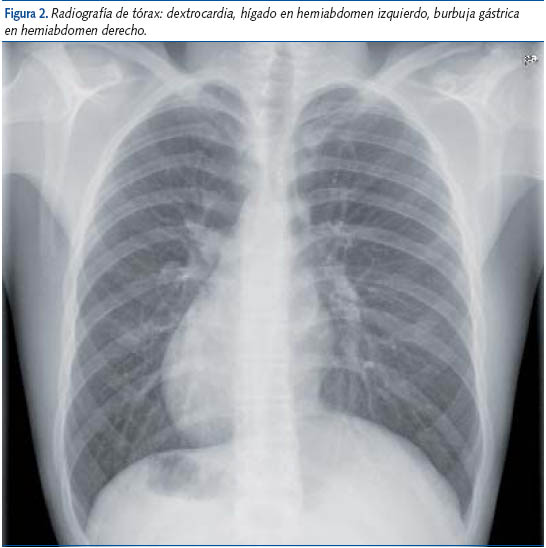

Estos hallazgos electrocardiográficos sólo pueden deberse a una incorrecta colocación de la totalidad de los electrodos (en el hemitórax equivocado) o a la existencia de dextrocardia (ubicación del corazón en el hemitórax derecho). El dato auscultatorio fue la presencia de los tonos cardíacos en el hemitórax derecho; asimismo, en la radiografía de tórax se objetivó dextrocardia, hígado situado en hemiabdomen izquierdo y burbuja gástrica en hemiabdomen derecho. Con la confirmación de situs inversus totalis, el niño fue remitido a cardiología infantil para descartar la presencia de una cardiopatía congénita.